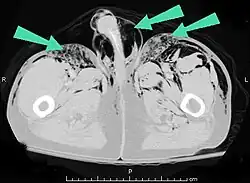

Additionally, it may result from self-injection of air during illicit drug use, particularly in individuals who inject substances intravenously or into unusual sites. There have been documented cases of subcutaneous emphysema occurring in various body regions, including the scrotum, secondary to such self-induced air injection during substance abuse.[23]

Air can be trapped under the skin in necrotizing infections such as gangrene, occurring as a late sign in gas gangrene,[2] of which it is the hallmark sign. Subcutaneous emphysema is also considered a hallmark of Fournier gangrene.[27] Symptoms of subcutaneous emphysema can result when infectious organisms produce gas by fermentation. When emphysema occurs due to infection, signs that the infection is systemic (i.e. that it has spread beyond the initial location) are also present.[9][21]